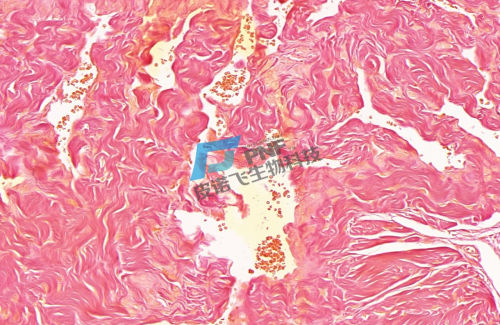

Van Gieson染色,简称VG染色,常用于区分胶原纤维和肌纤维,染色原理与阴离子染料分子的大小和组织的渗透有关。未脱钙骨组织切片经VG染色后,胶原纤维呈红色或鲜红色,肌纤维及背景呈黄色。

VG染色-小阴茎

胶原纤维呈红色或鲜红色,肌纤维及背景呈黄色。